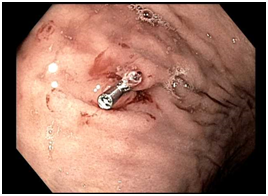

A 71year old woman with a past medical history of hypertension, gastroesophageal reflux disease and chronic epigastric pain was presented to the emergency room with complaint of melena and dizziness. She had undergone upper GI endoscopy and colonoscopy as an outpatient the day prior to presentation. Her upper GI endoscopy revealed a normal esophagus, stomach and duodenum. Biopsies of the gastric body and antrum were taken for evaluation of Helicobacter Pylori. She reported doing well after the procedures and was subsequently discharged from the endoscopy center. She was able to tolerate dinner that evening, but immediately had a large watery melenic stool. Furthermore, the morning prior to presentation, she experienced dizziness and lightheadedness, resulting in her admittance to the emergency room. The patient’s hemoglobin was found to be 6.7g/dL, which was down from her baseline of 12.7g/dL in January of 2016. Upper GI endoscopy revealed several linear erosions consistent with prior biopsy sites in the gastric body and antrum. One of these linear lesions had a prominent protruding non-bleeding visible vessel, which was subsequently washed thoroughly and treated with a hemoclip. The patient was then placed on Pantoprazole and monitored for 48hours in the hospital, with steady hemoglobin. In addition, she did not experience any melenic stools while in the hospital, and later was discharged home in stable condition (Figure 1) (Figure 2).

Figure 2